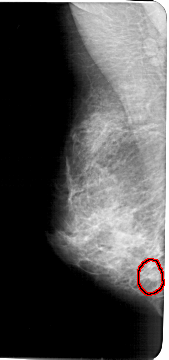

FILE: A_1459_1.LEFT_MLO.OVERLAY

TOTAL_ABNORMALITIES 1

ABNORMALITY 1

LESION_TYPE MASS SHAPE ROUND MARGINS CIRCUMSCRIBED

ASSESSMENT 4

SUBTLETY 3

PATHOLOGY BENIGN

TOTAL_OUTLINES 1

BOUNDARY